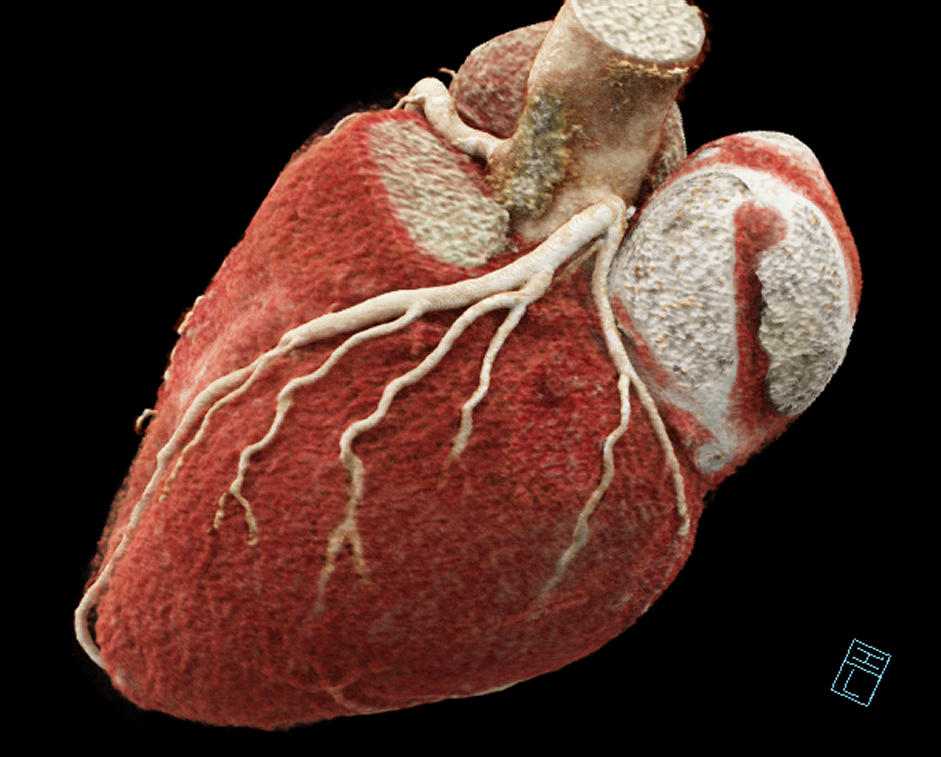

Tomografía de Corazón y Arterias Coronarias

Es un estudio de imagen no invasivo que permite evaluar el estado actual de las arterias coronarias en pacientes con síntomas como dolor torácico o dificultad respiratoria, con el objetivo de determinar si estos síntomas son causados o no por obstrucción en las arterias coronarias.

Permite evaluar la anatomía del corazón en pacientes con cardiopatías congénitas, válvulas protésicas, tumores cardiacos o que afectan las estructuras cardiacas. Se realiza mediante la adquisición y reconstrucción de imágenes demostrativas y mediciones que son de gran utilidad para la planeación de procedimientos y tratamiento de las múltiples afecciones cardiovasculares.